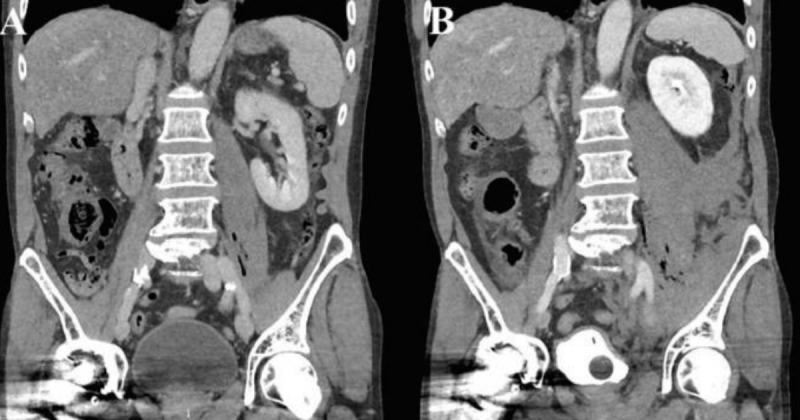

Exame de imagem mostra o acúmulo de líquidos e gases na área infectada – Foto: Science Direct/Reprodução/NDExame de imagem mostra o acúmulo de líquidos e gases na área infectada – Foto: Science Direct/Reprodução/ND

Após constatado que o homem não passara por nenhum trauma, os médicos o encaminharam para uma TC (tomografia computadorizada), que detectou fluídos e gás ao redor de um músculo que conecta as costas e as pernas.

Antes de ser submetido a alguma cirurgia, os responsáveis decidiram medicá-lo com antibióticos e observar, sendo levado para outra TC depois de duas horas e meia. O segundo exame mostrou uma piora dos sinais vitais e um aumento dos gases e fluídos no local infectado.